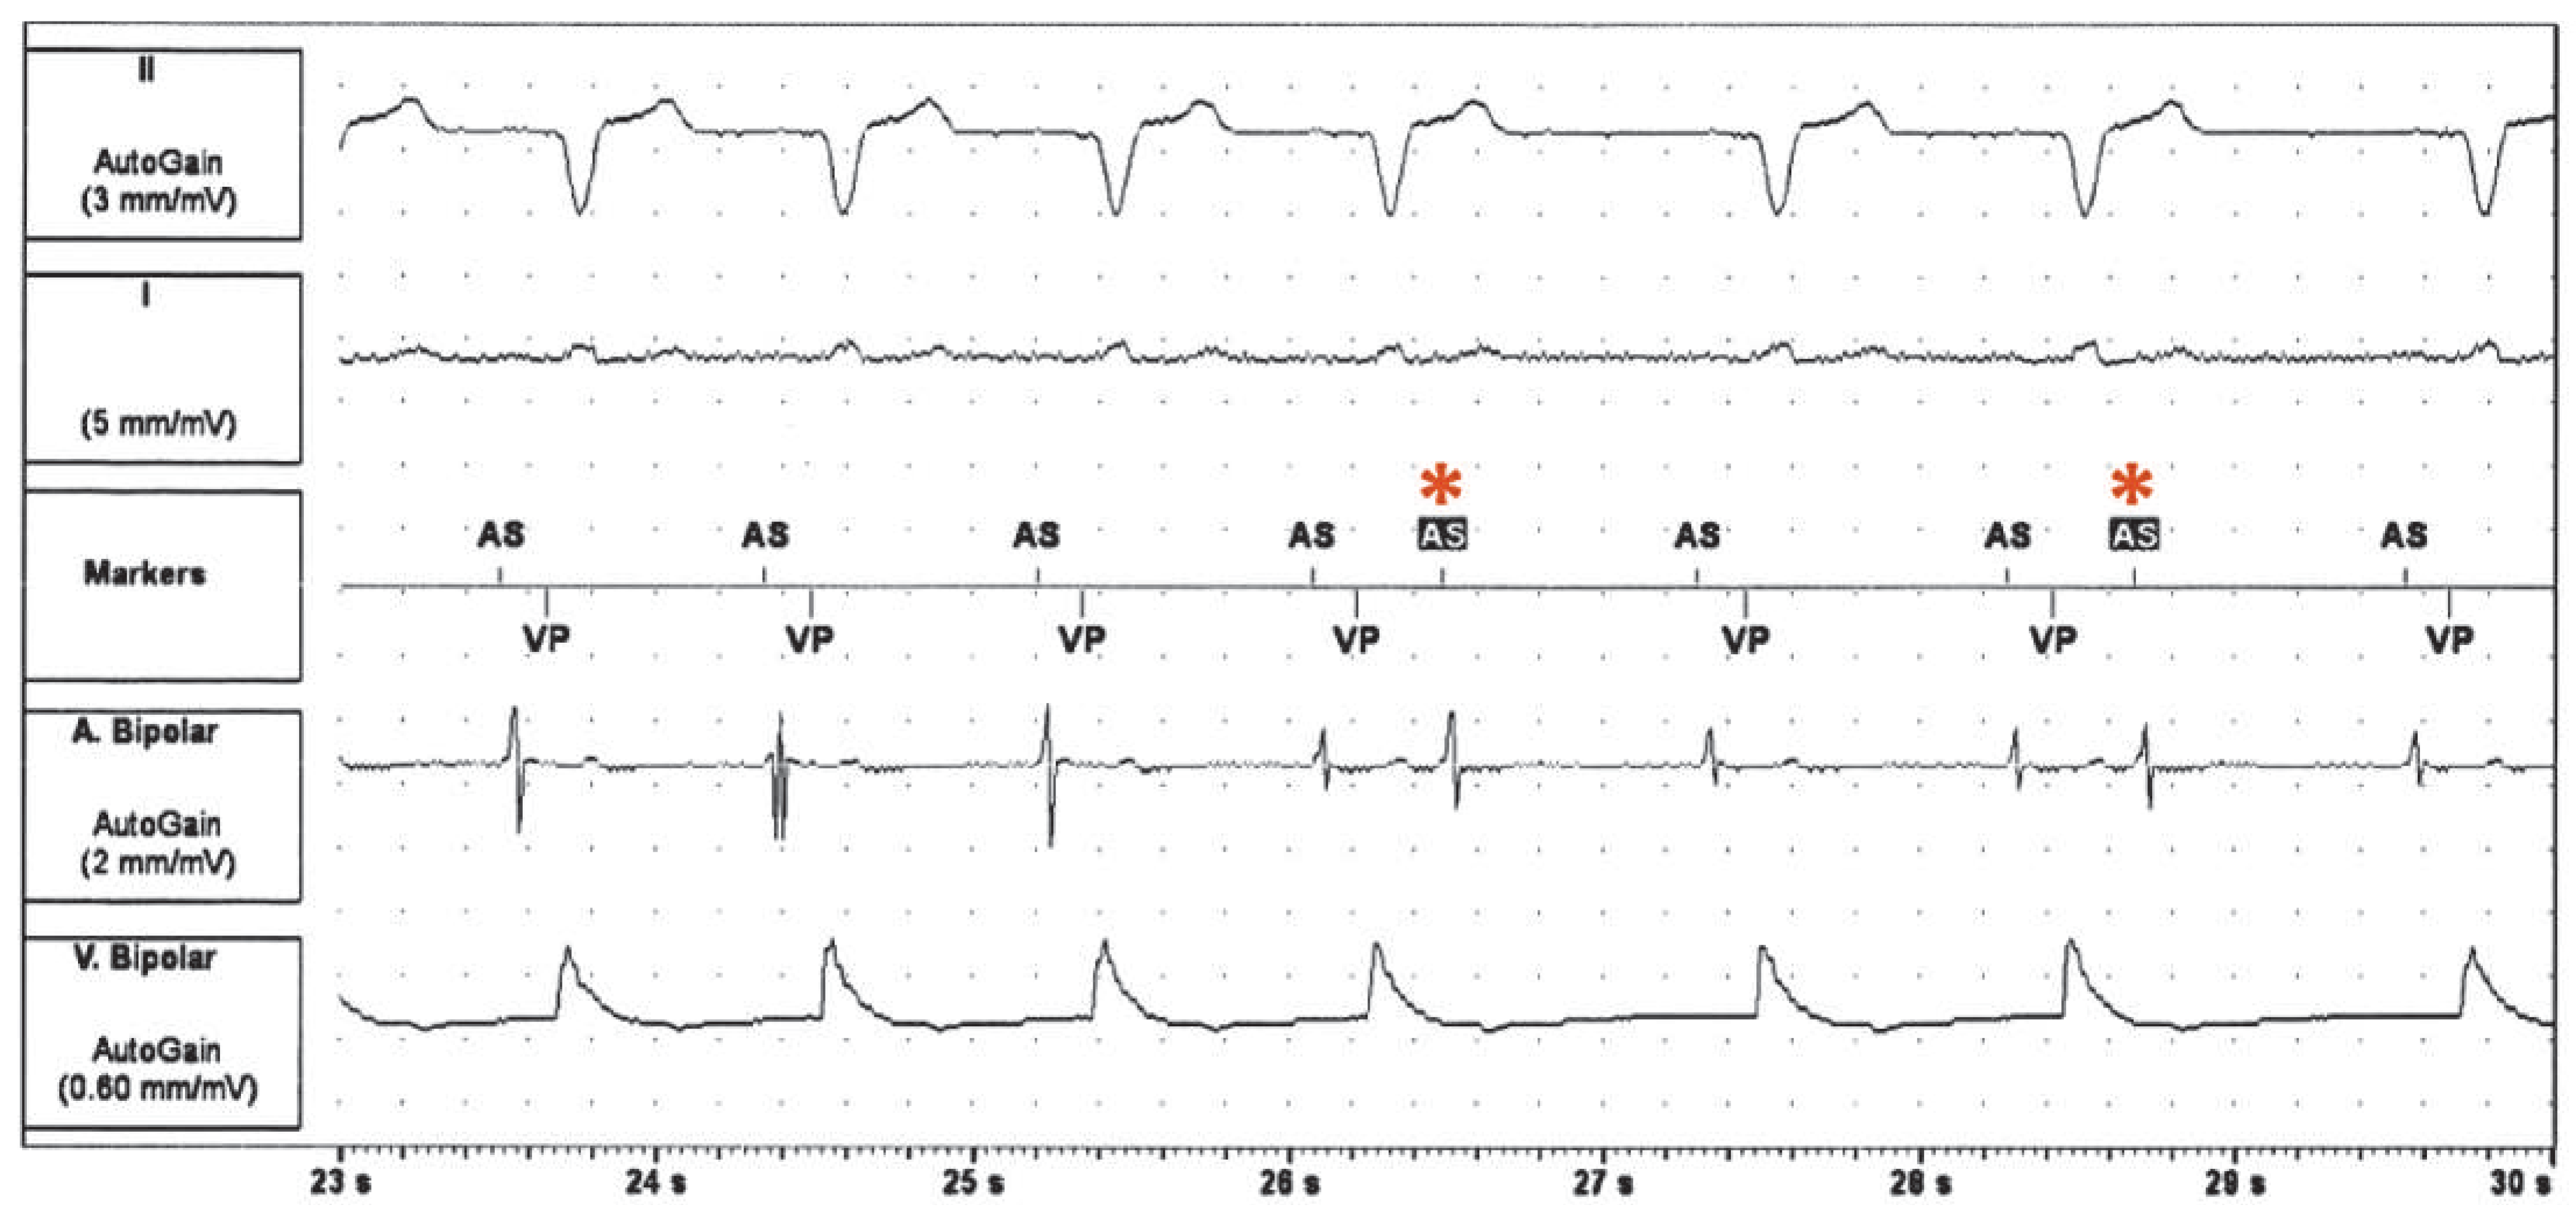

A 76-year-old man was seen in the pacemaker clinic for routine follow-up. He had undergone implantation of a dual-chamber pacemaker (SJM Verity ADx XL DR 5356) for bifascicular block and high-degree atrioventricular (AV) block on Holter-ECG after suffering syncope. After the implant, no more syncope occurred and the patient was feeling well. During the follow-up visit, recurrent runs of a tachycardia were observed (Figure 1), from which the patient was completely asymptomatic.

The tracing in Figure 1 shows a tachycardia with a CL of 500 ms and a 1:1 AV conduction. The tachycardia starts with a prematurely sensed atrial event (third atrial event on the tracing, marked * in Figure 2) and the tachycardia is tracked to the ventricle with an AV delay of 240 ms. During tachycardia, there is double ventricular farfield oversensing in the atrium. The first additional signal on the atrial channel, marked with a blue up-arrow in Figure 2, falls into the postventricular atrial blanking period (PVAB) and represents a farfield signal from the ventricular paced beat. The second oversensed signal (marked with a red down-arrow in Figure 2) is probably oversensing of the end of the QRS complex; T-wave oversensing is unlikely because it occurred even before the T-wave. This atrial signal falls into the postventricular atrial refractory period (PVARP).

Figure 1. Tachycardia observed during routine pacemaker interrogation. AP = atrial paced event; AMS = automated mode switch; AS = atrial sensed event; AS = atrial sensed event in the postventricular atrial refractory period (PVARP); VP = ventricular paced event.